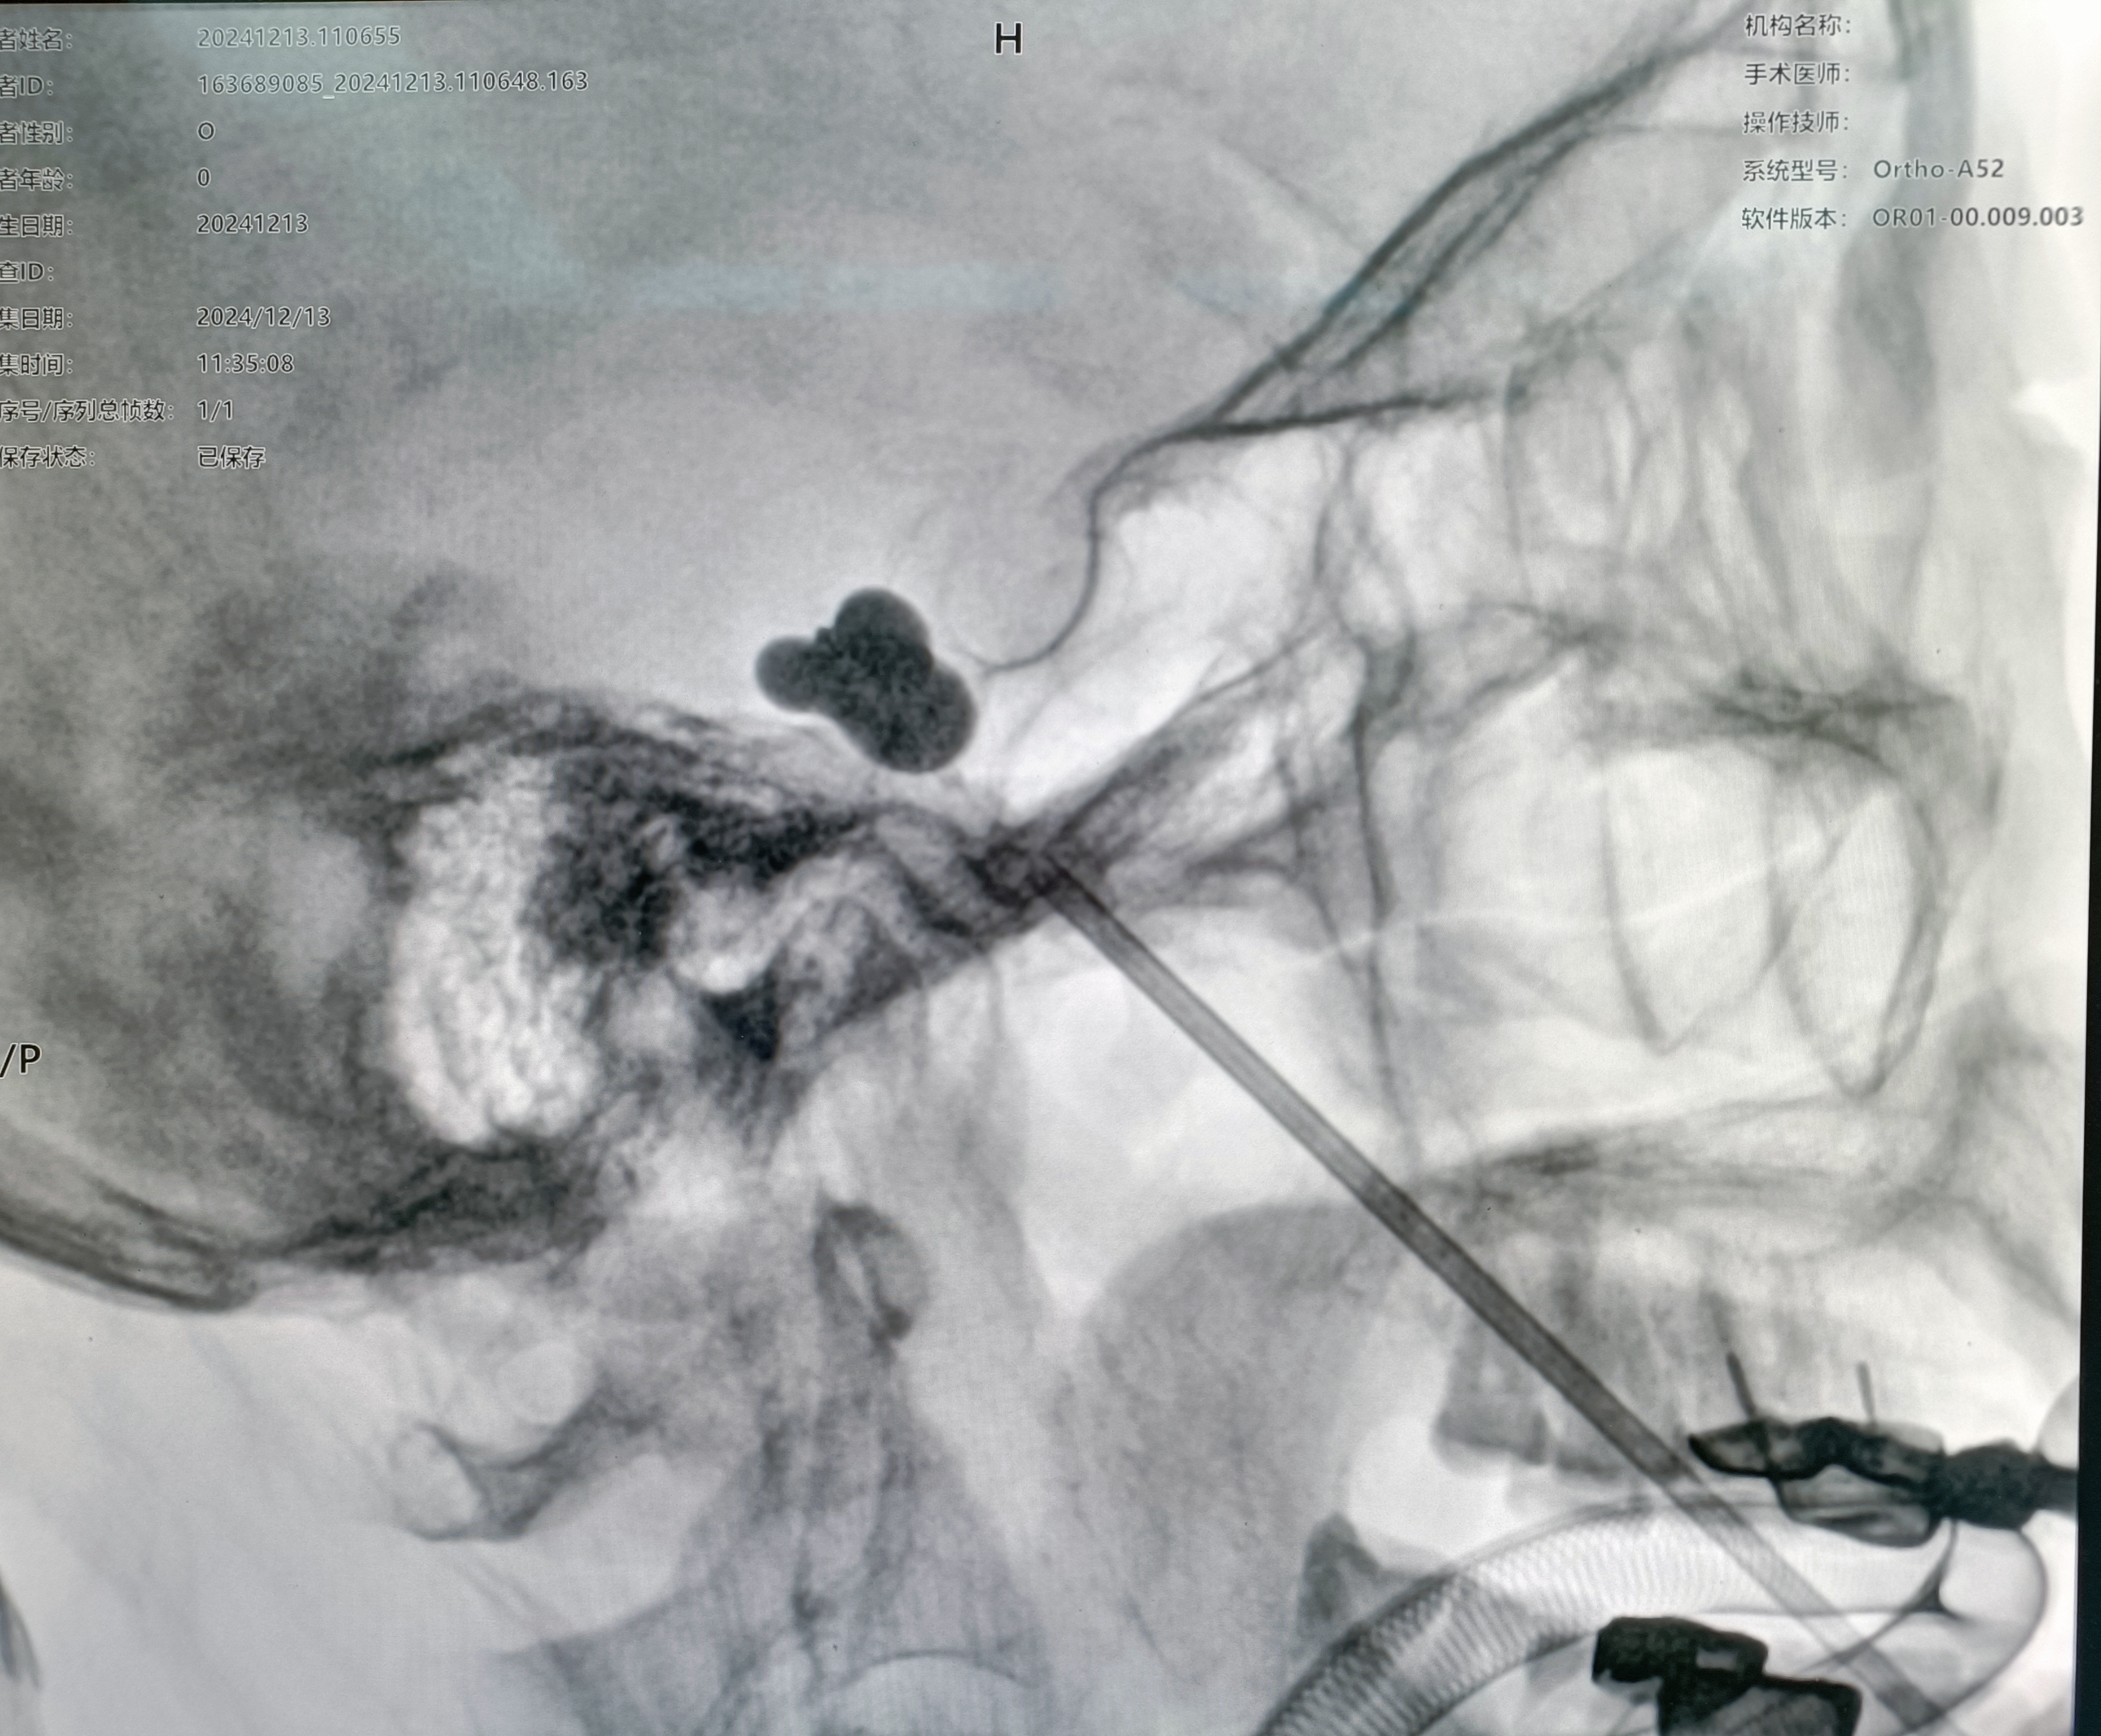

患者70岁女性,以右侧口角电击样疼痛6月为主诉入院,口服卡马西平早期有效,后增加药量后效果不佳,药物副作用症状明显,查体可见患者痛苦面容,消瘦,进食困难,不敢言语,言必痛。评估病情后家属要求行球囊压迫术。

术后自觉右侧颜面部麻木,右侧口角疼痛不明显。